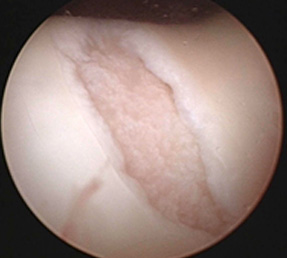

1.マイクロフラクチャー法

限局した比較的小さな軟骨損傷に対して効果的な方法です。軟骨損傷部の骨に非常に小さな幾つかの穴をつくることにより軟骨組織の下の骨髄を刺激し軟骨様組織の再生を促進する方法です。

マイクロフラクチャー法